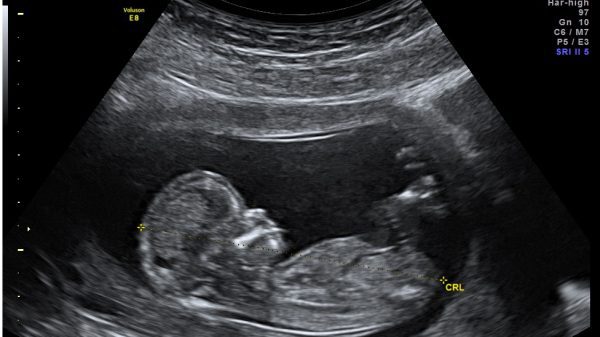

Por ejemplo, un manifiesto de Médicos por el Latido Fetal, que ha publicado la Fundación Más Vida. En el texto se constata que el feto tiene latido y que «este importante hecho sin duda constituye una parte fundamental de las que se deben considerar a la hora de plantearse la denominada Interrupción Legal del Embarazo (ILE): el embrión-feto tiene latido».